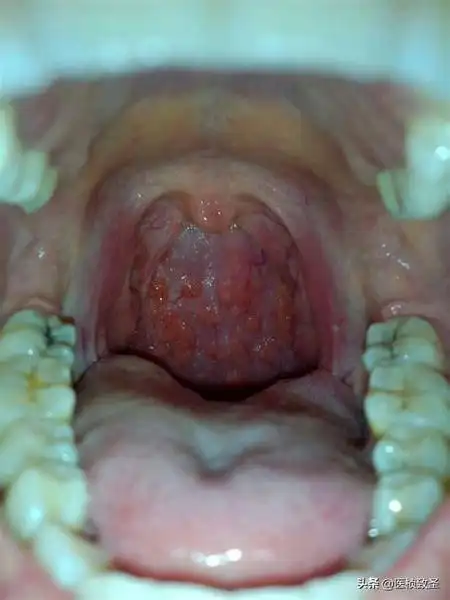

小孩嗓子嗓子老感觉有东西,老吭吭的怎么办?